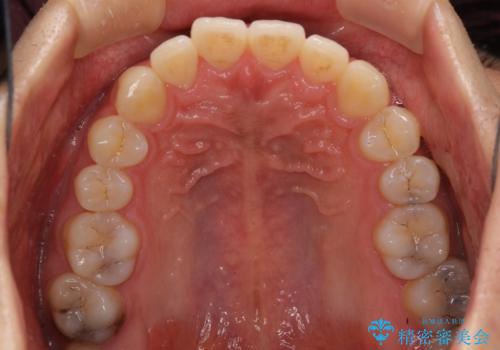

口が少し閉じにくい インビザラインによる非抜歯矯正

- 口元の突出感を治したいとのことで来院された患者様です。

上下顎ともにIPR(歯と歯の間を削る)と歯列全体の拡大によって口元が引っ込むように設計し、インビザラインにより治療を行うこととしました。

抜歯をして口元を下げなければならないほど出っ歯ではなかったため、少しずつ治療ゴールを変更しながら仕上げていきました。

気になっていた前歯の飛び出した印象は、最終的にはスッキリと引っ込み、大変満足していただきました。